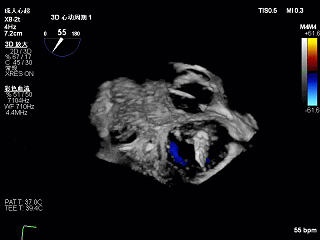

术前Bicom切面

术前X-Plane

术前瓣口面积5.39cm²

后叶长度9.24cm

可用房间隔穿刺高度4.03cm

3D-ZOOM 彩色多普勒显示反流主要来源于2区